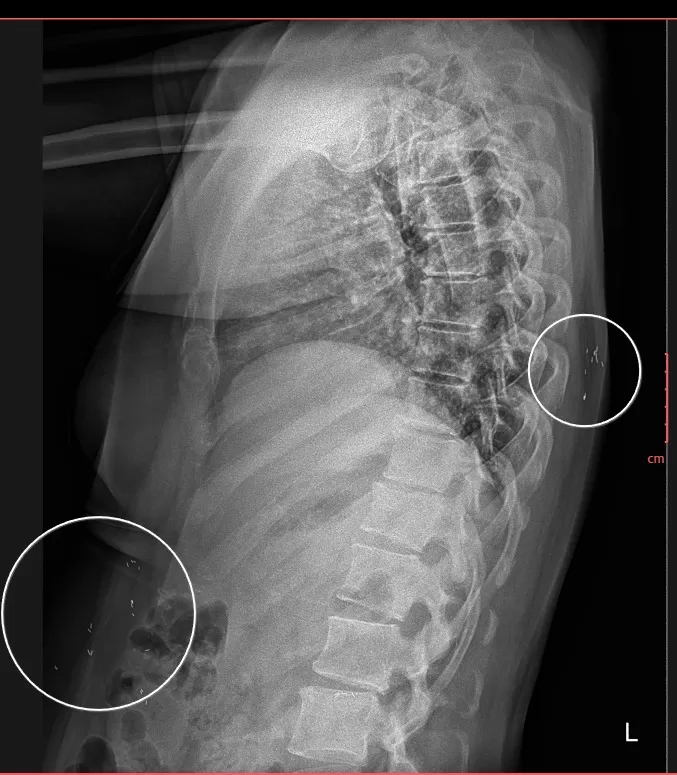

📸 Hình ảnh X-quang thường quy (đính kèm) cho thấy:

-

Nhiều nốt cản quang nhỏ, hình dạng thoi/hạt gạo,

Phân bố rải rác trong mô mềm và các khối cơ vùng ngực, bụng và thành bụng,

Các tổn thương không liên quan đến cấu trúc xương khớp.

➡️ Đây là hình ảnh điển hình gợi ý nhiễm ký sinh trùng dạng kén, đặc biệt là kén sán, một bệnh lý dễ bị chẩn đoán nhầm do triệu chứng lâm sàng không đặc hiệu.